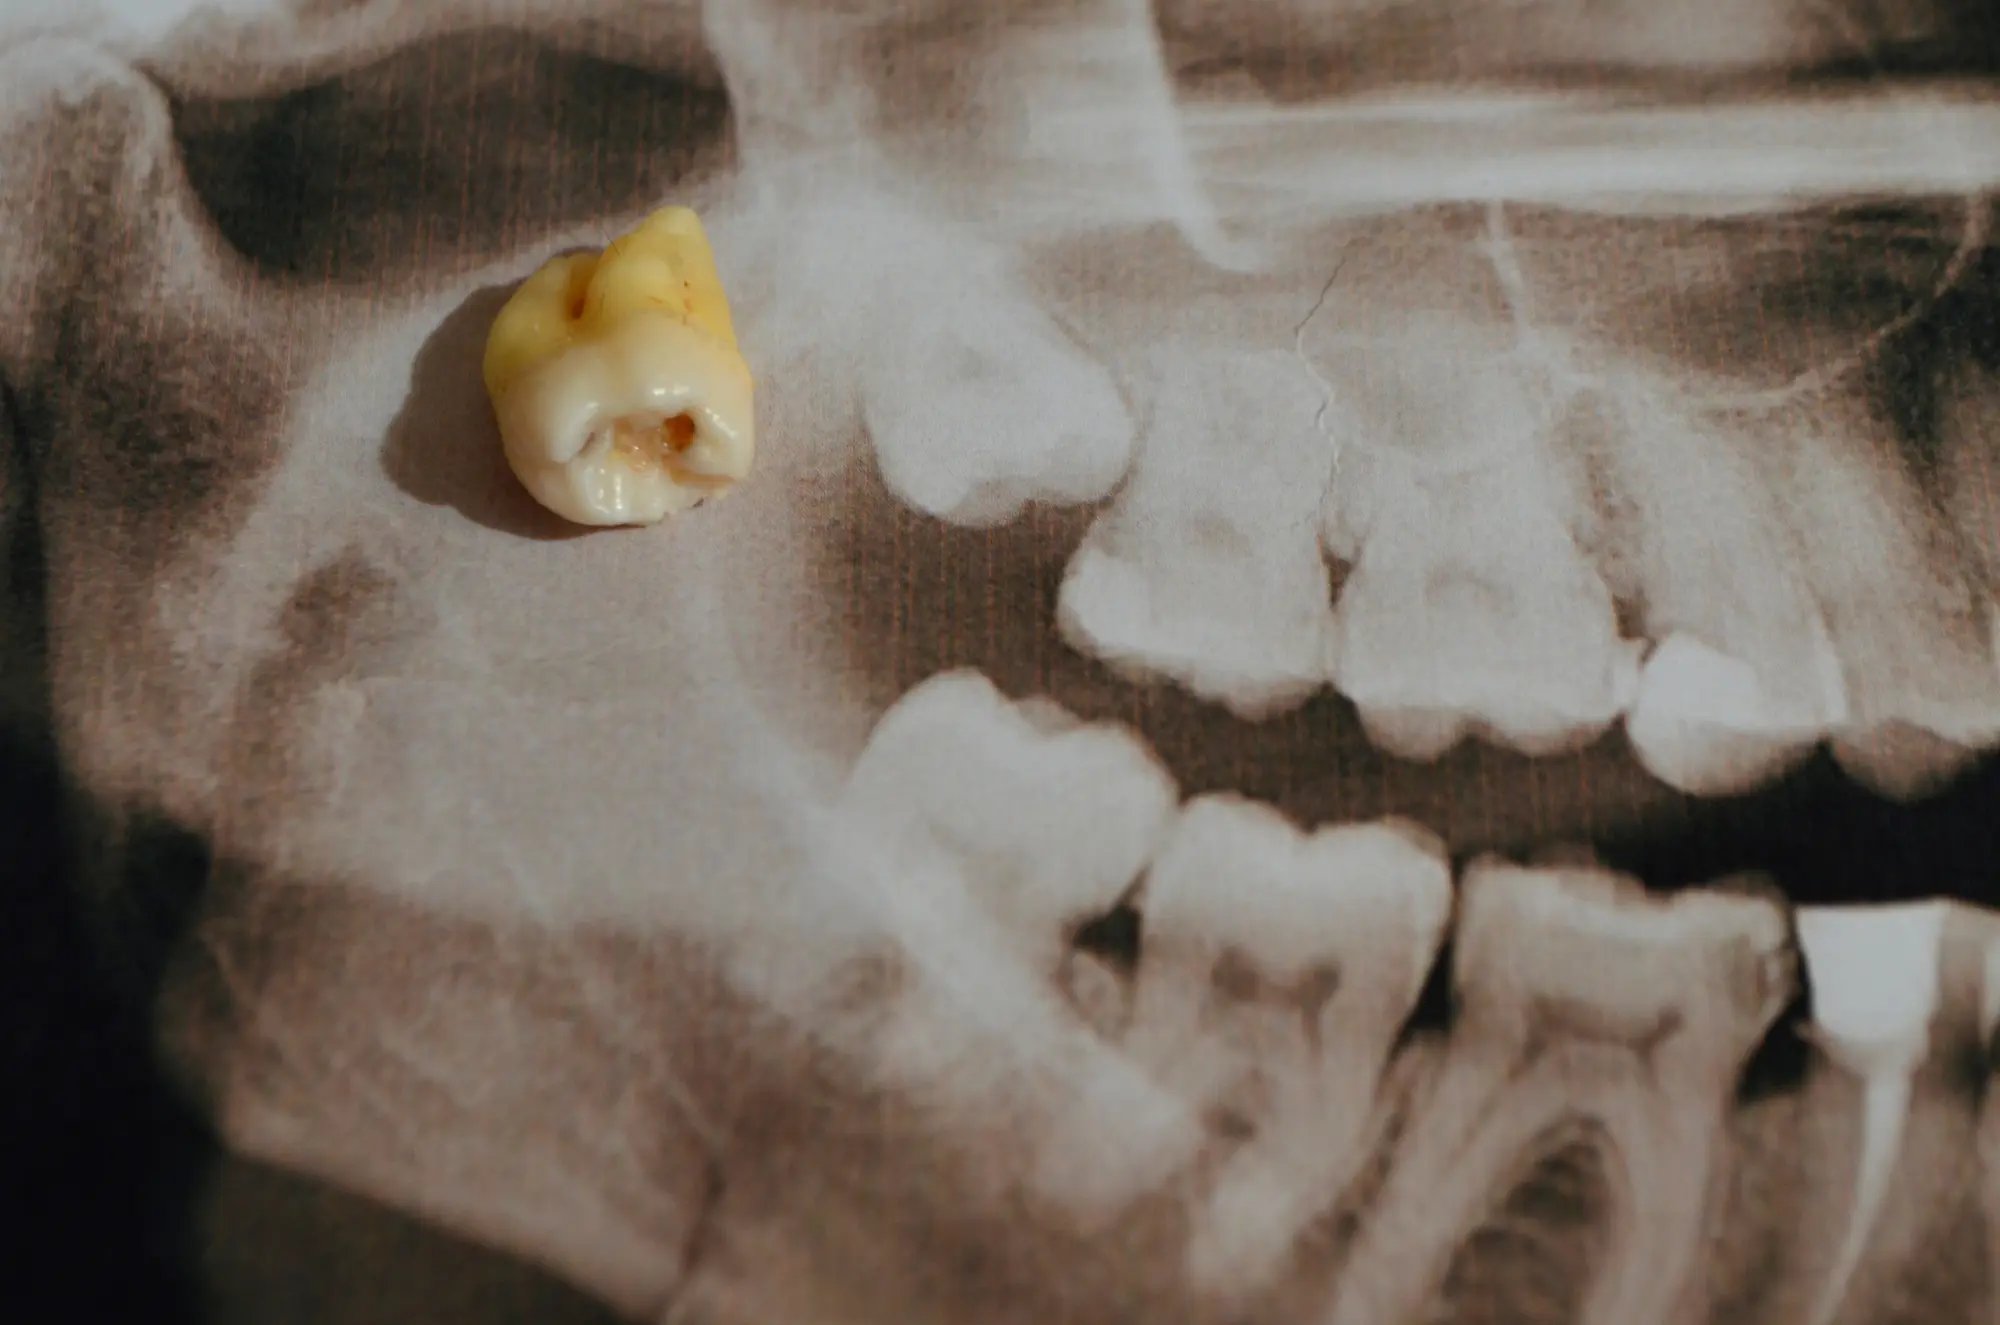

However, many people experience crowding, impaction (when the tooth doesn’t fully emerge), or increased risk of infection and decay. Regular exams and X-rays help determine whether your wisdom teeth could cause future problems.

Your first visit includes a thorough exam and digital X-rays to see the position of your wisdom teeth and how they’re affecting your oral health. Dr. Rintel will explain whether removal is recommended, and if so, discuss your options for anesthesia and recovery.